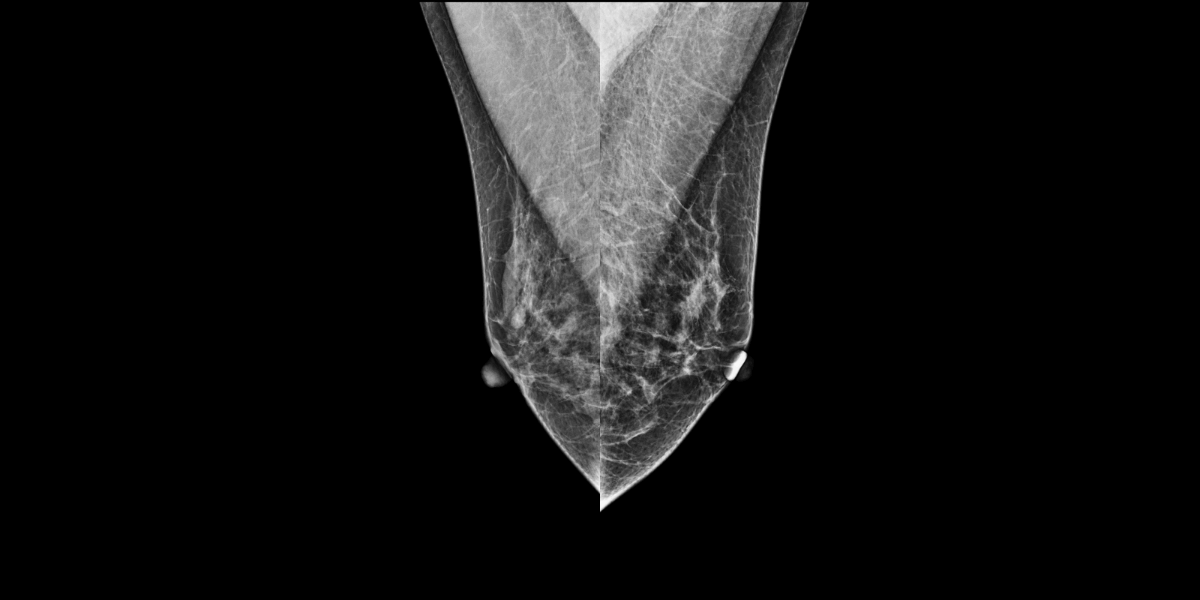

Lors du dépistage, deux masses ont été trouvées, l’une sur le sein droit (2cm DTN) et l’autre sur le sein gauche (A1 cm DTN), catégorisée comme suspecte.

La patiente a été rappelée pour une échographie. La biopsie réalisée a montré un cancer lobulaire infiltrant sur le sein gauche (deux masses).